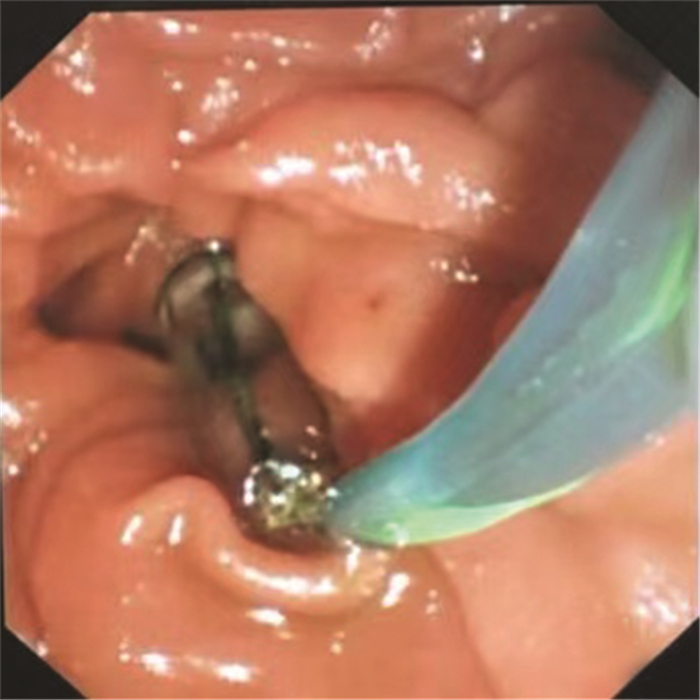

Consensus on imaging techniques and diagnostic criteria for hepatitis B virus related early hepatocellular carcinoma

Radiology of Infection Sub-branch, Radiology Branch, Chinese Medical Association, Committee on Radiology of Infection, Radiology Branch, Chinese Medical Doctor Association, Radiology Committee on Infectious and Inflammatory Disease, Chinese Research Hospital Association, Radiology of Infection Branch, Working and Treating Committee of HIV/AIDS and STD Association, Radiology of Infectious Disease Management Sub-branch, Infectious Disease Management Branch, Hospital Management Association in China, Beijing Imaging Diagnosis and Treatment Technology Innovation Alliance

2021, 37(4): 787-791. DOI: 10.3969/j.issn.1001-5256.2021.04.013

Abstract(1427) HTML (513) PDF (4471KB)(236)

Abstract:

The pathological diagnostic criteria for early hepatocellular carcinoma(eHCC)have been updated in 2009, but the imaging diagnostic criteria for eHCC have not yet been established by domestic or foreign academic organizations. Promoted by Radiology of Infection Sub-branch, Radiology Branch, Chinese Medical Association, associating with Committee on Radiology of Infection, Radiology Branch, Chinese Medical Doctor Association; Radiology Committee on Infectious and Inflammatory Disease, Chinese Research Hospital Association; Radiology of Infection Branch, Working and Treating Committee of HIV/AIDS and STD Association; Radiology of Infectious Disease Management Sub-branch, Infectious Disease Management Branch, Hospital Management Association in China; Beijing Imaging Diagnosis and Treatment Technology Innovation Alliance, this consensus was formed under the efforts of more than 40 experts from more than 10 domestic provinces and cities, so as to help related professional doctors in diagnosis of eHCC.